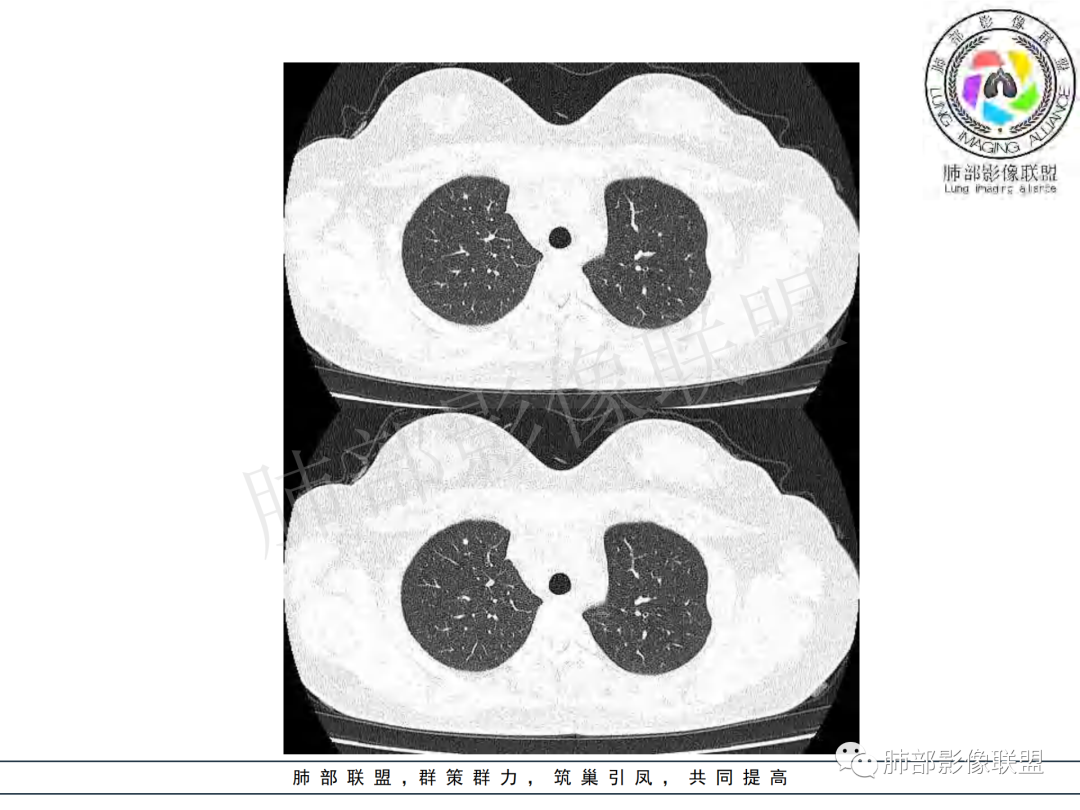

病例展示

右肺肺门旁肿块,右肺中间段支气管腔内结节,增强强化不均;纵隔多发淋巴结环形强化,右侧少量胸腔积液,临床发热入院,考虑结核,鉴别肿瘤。

右肺门增大,远端花花草草不明显,支气管管壁增厚,纵隔淋巴结环形强化,年龄,病程,考虑炎性病变,结核可能,有个层面支气管截断,有强化,鉴别粘表。

女,20,病程长达8月,发热、胸痛、右侧胸腔积液病史。胸部CT:右肺门旁不规则肿块影,右中间支气管腔内结节,纵隔多发淋巴结肿大;强化不均匀,灶性坏死灶,环形强化;右侧少量胸腔积液并局部肉芽肿样突起。年轻女性,长病程,多部位,考虑慢性炎症,结核?鉴别肿瘤。

青年,右肺门增大,见软组织肿块影,部分支气管腔结节,并管腔狭窄,增强后明显不均匀强化,伴纵隔多发肿大淋巴结,环形强化,考虑恶性,类癌,鉴别支气管内膜结核

右肺门不规则肿块,向气管腔内生长,不均匀强化,其内粘液栓,纵隔淋巴结增大,部分有坏死,胸膜结节强化,考虑恶性,粘表?类癌?鉴别结核

右肺肺门旁肿块,右肺中间段支气管腔内结节,增强强化不均;纵隔多发淋巴结环形强化,右侧少量胸腔积液,考虑结核可能,鉴别肿瘤。

年轻女性,慢性病程,发热、胸痛。右肺门旁不规则肿块影,纵隔多发淋巴结肿大;强化不均匀,环形强化;右侧少量胸腔积液;首先考虑结核,鉴别肿瘤,结节病。

女性,20岁。高热、畏寒。右肺上叶近肺门区不规则肿块,周围斑点、片小结节影伴肿大淋巴结,肿块包绕并突入右主支气管腔内,增强后肿块不均匀强化,淋巴结环形强化中心低密度,考虑结核。